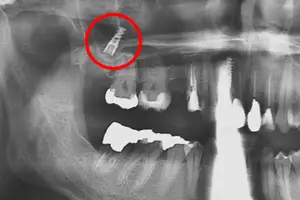

下顎の骨には、下顎管という下歯槽神経が通る管があります。この神経に埋入したインプラント触れてしまったり手術で傷つけてしまうと、顎や唇に麻痺を起こすことがあります。

そのために、インプラント治療前にはレントゲンだけではなく、CT検査により顎の骨と神経との位置関係を把握しておく必要があります。

上顎の骨の上には、上顎洞という空洞があります。

インプラント手術時、骨質が弱かったり骨の量が少なかったり、CTで骨の状態を確認していなければ、埋入したインプラントが顎の骨を貫通し、上顎洞に迷入することがあります。